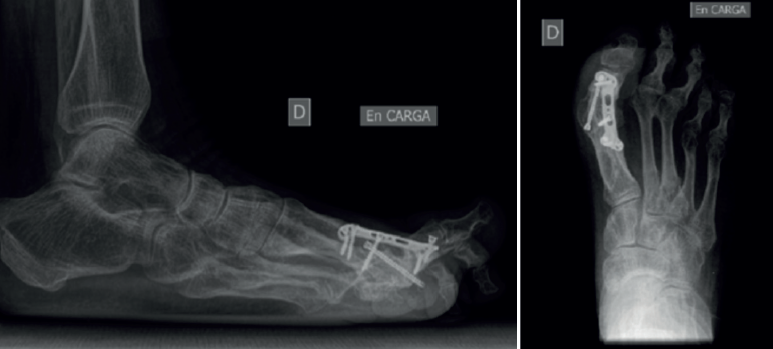

Entre febrero de 2022 y junio de 2023, hubo 7 procedimientos de este tipo realizados por el primer autor. Había 6 mujeres y 1 hombre, con una edad media de 64,8 años (rango: 56-71) en el momento de la cirugía (Tabla 1). No se excluyó a ningún paciente del estudio y ninguno se perdió durante el seguimiento. De los pacientes, 5 sufrían dolor (sin fusión) tras el fracaso de una artrodesis de la MTF1 previa con pérdida ósea limitada (Figura 1); 2 pacientes sufrieron dolor debido a hallux elevatus y en valgo tras una artrodesis de la MTF1 con consolidación viciada (Figura 2).

Se utilizó una sierra motorizada para la extracción del injerto corticoesponjoso. La parte cortical es un rectángulo dibujado en la superficie dorsal del primer metatarsiano y de sección triangular (Figura 3). Se realiza una extracción con forma similar en el dorso de la primera falange (Figura 4). Esto genera una cavidad en forma de cuña desde el primer metatarsiano hasta la primera falange (Figura 5). A continuación, el injerto obtenido del primer metatarsiano se moviliza distalmente y se encastra en la cavidad ósea, tendiendo un puente entre los dos huesos (Figura 6). La posición del dedo del pie se evalúa contra una superficie plana para simular la situación de soporte de peso, como en una artrodesis estándar. Se colocan agujas de Kirschner para estabilizar provisionalmente la MTF1. Para rellenar el hueco óseo proximal del primer metatarsiano puede utilizarse el hueso extraído de la falange o un sustituto óseo. Se realizó una fijación con placa de bloqueo dorsal de la MTF1 y con al menos un tornillo de compresión interfragmentaria (Figuras 7 y 8). Se realizó una cirugía simultánea en los dedos menores cuando estaba indicado. La herida se cerró y se vendó de la forma habitual. En caso de deformidad asociada del primer dedo en valgo, se extrajo una cuña ósea de localización supramaleolar interna que se añadió a la reconstrucción previa (Figura 9).

La curación se determinó mediante examen clínico (disminución progresiva del dolor y consolidación progresiva de la artrodesis de la MTF1) y evidencia radiográfica de una fusión sólida (vistas anteroposterior y lateral del pie en bipedestación) en ausencia de dolor a la movilización en la MTF1 a las 12 semanas del postoperatorio.